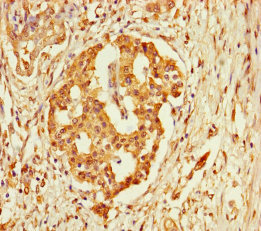

Immunohistochemistry of paraffin-embedded human pancreatic cancer using CSB-PA687502LA01HU at dilution of 1:100